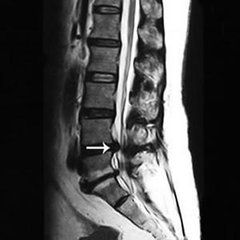

导读: 椎管狭窄在老年人当中比较常见的骨科疾病,椎管狭窄引起的跛行是指病人直立或行走时,下肢有逐渐加重的沉重感、疼痛、麻木、乏力等不同的感觉,以至于不得不改变姿势或停止行走。

导读: 腰椎滑脱是由于先天性发育不良、创伤、劳损等原因造成相邻椎体骨性连接异常而发生的上位椎体与下位椎体部分或全部滑移,表现为腰骶部疼痛、坐骨神经受累、间歇性跛行等症状的疾病。

导读:  很多患了骨病的人会出现走路跛行的情况,一般引起跛行的疾病主要有腰椎间盘突出、股骨头坏死和腰椎管狭窄等疾病,那么腰椎管狭窄为什么会引起走路跛行呢?为此云南骨科医院专家介绍说: